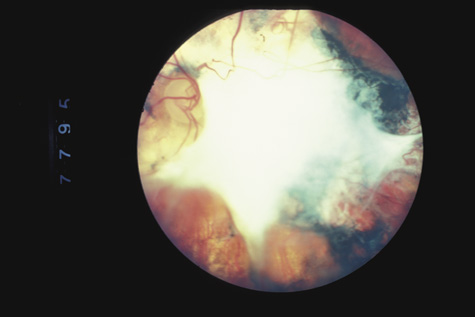

Retinitis sclopeteria is the rupture of the choroid or retina caused by shock waves generated by passage of a high-velocity missile through the orbit without directly striking the eye. Initially a subretinal or vitreous hemorrhage is seen. If the optic nerve is damaged, visual acuity can be profoundly decreased. In severe cases, massive amounts of fibrous tissue proliferate into the eye (Fig. 27). In others, as the blood clears, a claw-like break is often seen in Bruch's membrane and in the choriocapillaris (Fig. 28). Retinal detachment rarely occurs at the site of the injury, probably because of binding of the retina to the choroid by fibrous tissue, but late detachment from a break at a distal site can occur.97,98

Fig. 27. A: the left eye of a man who shot himself with a pistol. The bullet passed through both orbits, behind the globes. The optic nerve is at the left of the photograph. There is extensive fibrous proliferation. B: The right eye has considerably less retinal damage, but the visual acuity is hand movements because of optic atrophy.

Fig. 28. A: An equator plus photograph shows retinitis sclopeteria. B: Higher power view of the sclopeteria.